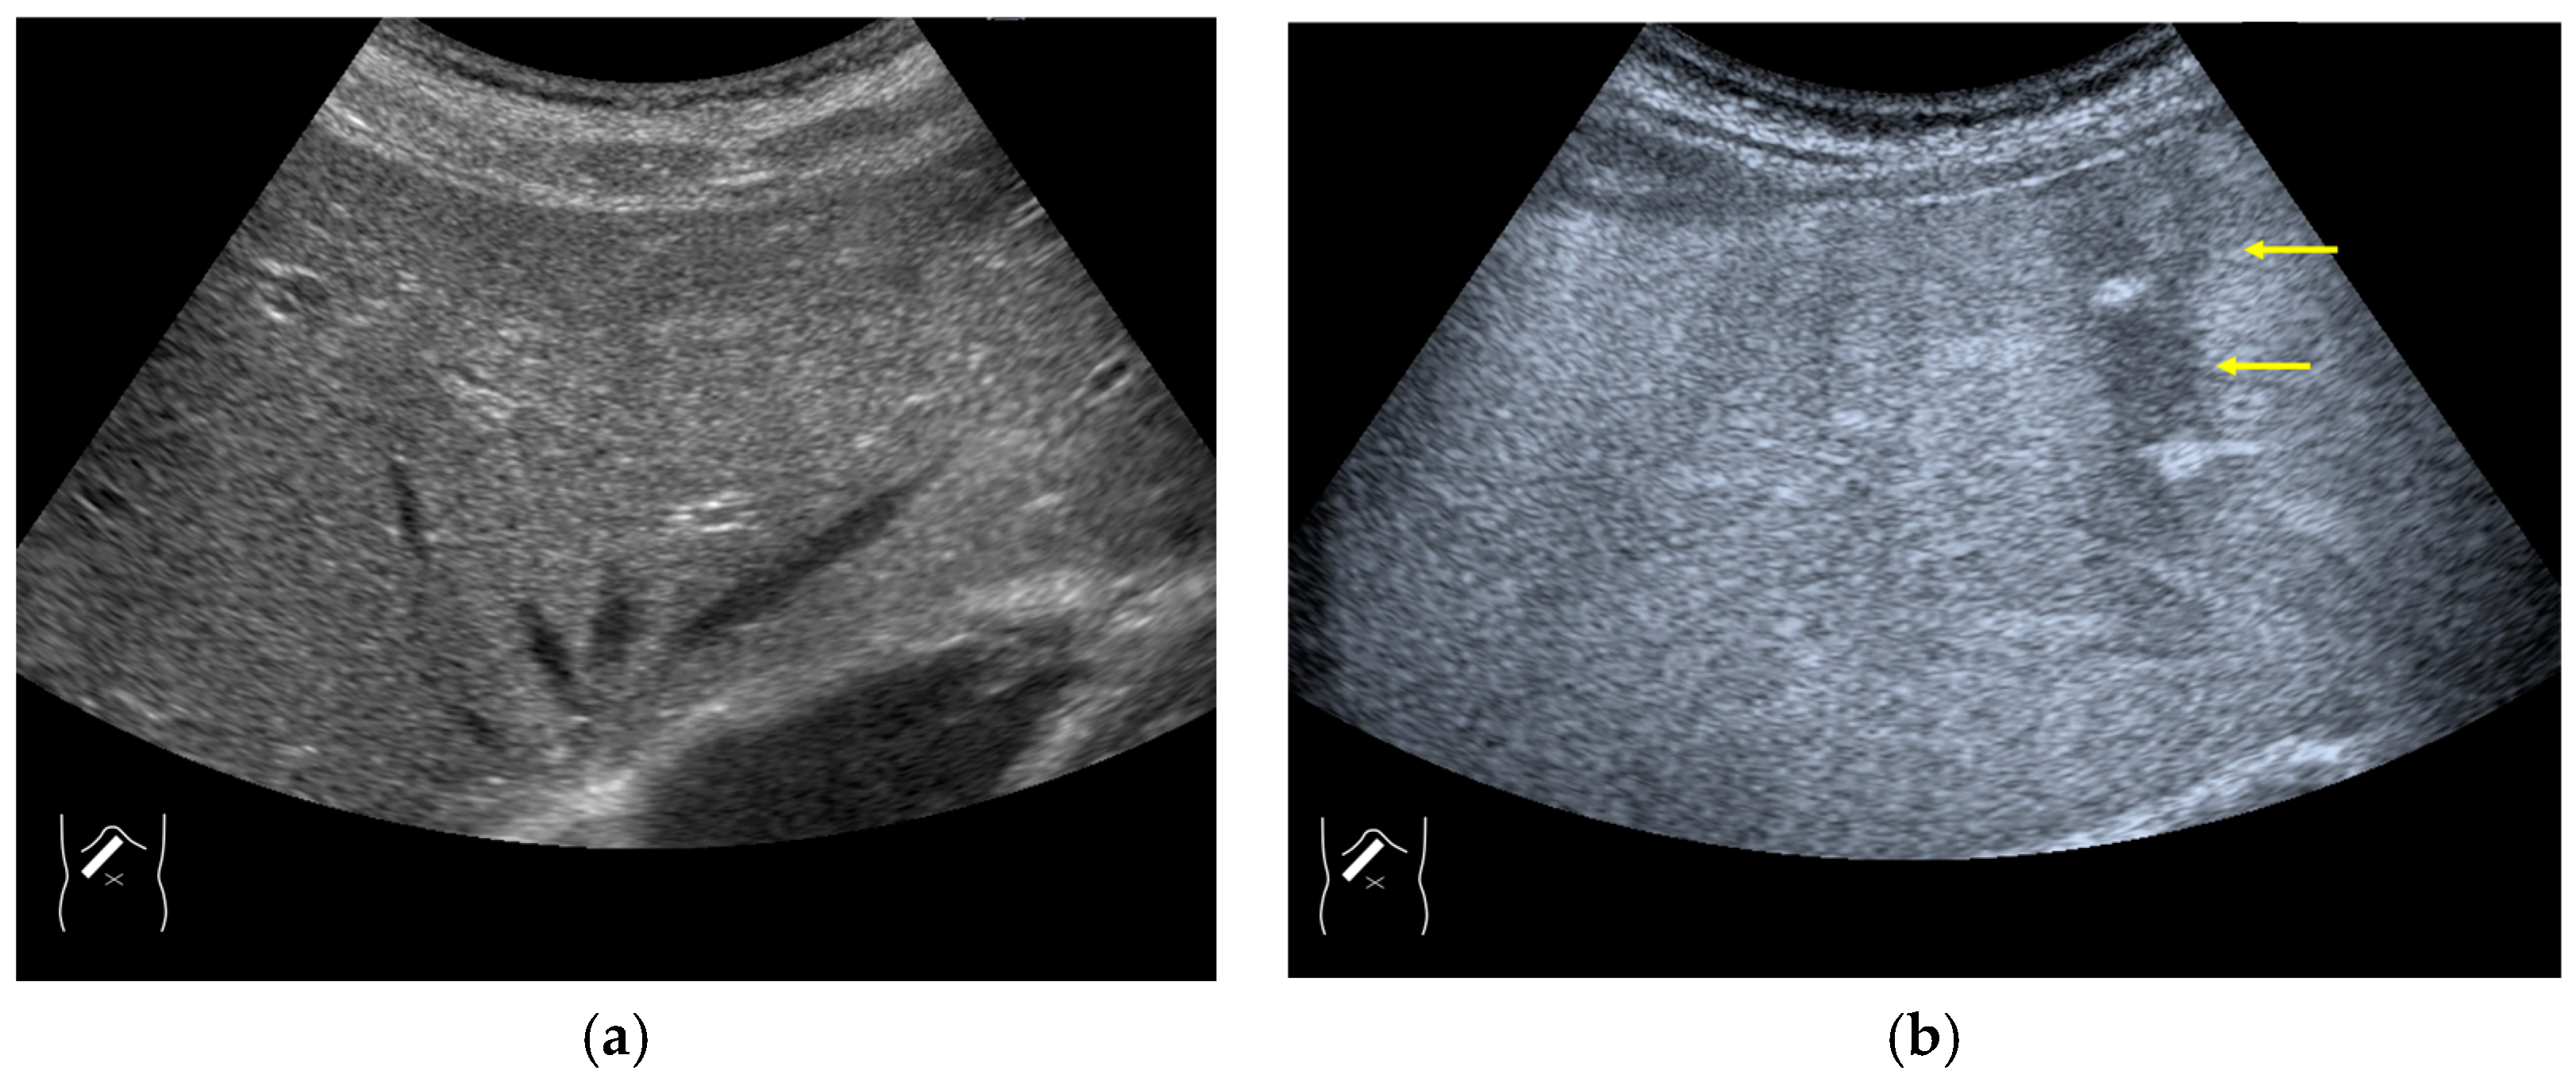

There are two sources of sound attenuation in the human body, (a) reflection and sound scattering and (b) sound absorption [47]. Both factors contribute to the formation of attenuation artifacts. These artifacts mainly occur in difficult patients (e.g., patients with advanced liver cirrhosis, patients with obesity, and patients with severe fatty liver) [48,49,50]. Increasing the mechanical index (M.I.) is not recommended for overcoming this attenuation artifact because an excessively increased M.I. causes visible microbubble destruction at the hepatic surface. Generally speaking, US attenuation in soft tissues is highly dependent on the US frequency and is nearly proportional to it (Figure 6). Less attenuation with a lower frequency results in an increased penetration depth. Thus, the most useful strategy is to use a transducer with a lower transmission frequency at the expense of a slightly deteriorated image quality (Figure 7). Another diagnostic strategy is to adjust the STC 3), which slightly improves the visualization of deep areas (Figure 8). We present herein a representative case of a “pseudo-tumor” in a decompensated cirrhotic patient where less attenuated US beams passing through the ascites mimicked an echogenic tumor at the periphery of the liver not only in B-mode US but also in CEUS (Figure 9).

Figure 7.

Hypoenhanced area due to sound attenuation. (a) Gray-scale US of the liver (L) in a patient with alcoholic liver cirrhosis. (b) CEUS (4 MHz) shows that the deep area is hypoenhanced (*) compared with the upper area. (c) CEUS (3 MHz) shows the liver to be homogeneously enhanced.

Figure 9.

Representative case of a sound attenuation artifact. The presence of massive ascites leads to US beams passing through less attenuated ascites, mimicking an echogenic liver tumor (arrows). (a) B-mode US and (b) CEUS.